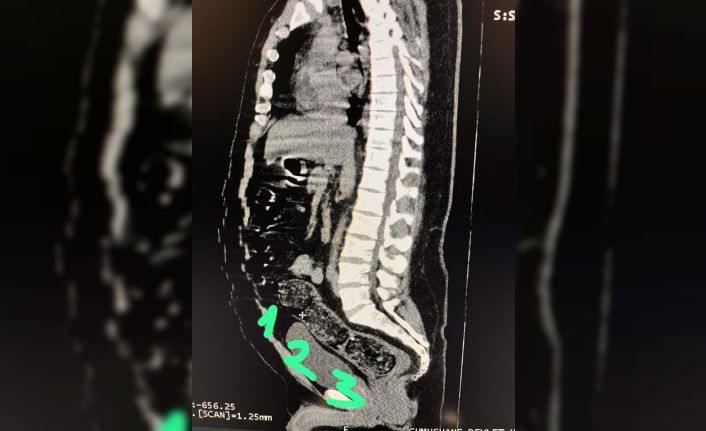

Adli makamların talimatı üzerine Gümüşhane Devlet Hastanesine götürülen şahsa yönelik iç beden muayenesinde bağırsaklarında 3 adet kapsül olduğu tespit edildi. Hastanede yapılan müdahalenin ardından şahsın bağırsaklarından çıkarılan kapsüllerin içerisinde toplamda 271,55 gram metamfetamin ele geçirildi.